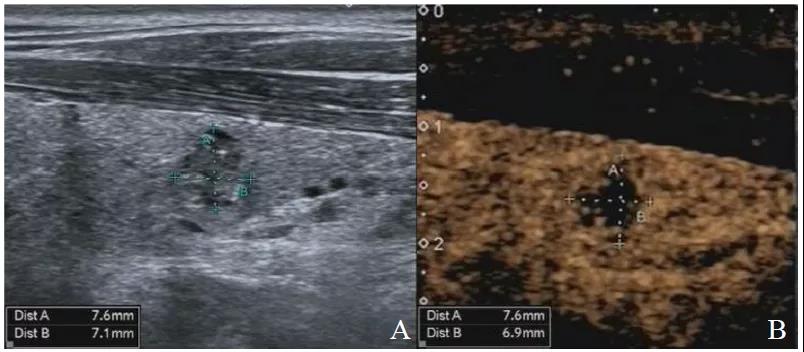

图1显示PTMC组结节大小的CEUS测值小于灰阶超声测值,图2显示良性组结节大小的CEUS测值与灰阶超声测量相近。表2显示PTMC组结节大小的CEUS测值明显小于灰阶超声测值(P<0.05)、良性组结节大小的CEUS测值与灰阶超声测值差异无统计学意义(P>0.05)。

图2 良性组结节大小测量

注:CEUS测量与灰阶超声测值相近。A为灰阶超声图像;B为CEUS图像。